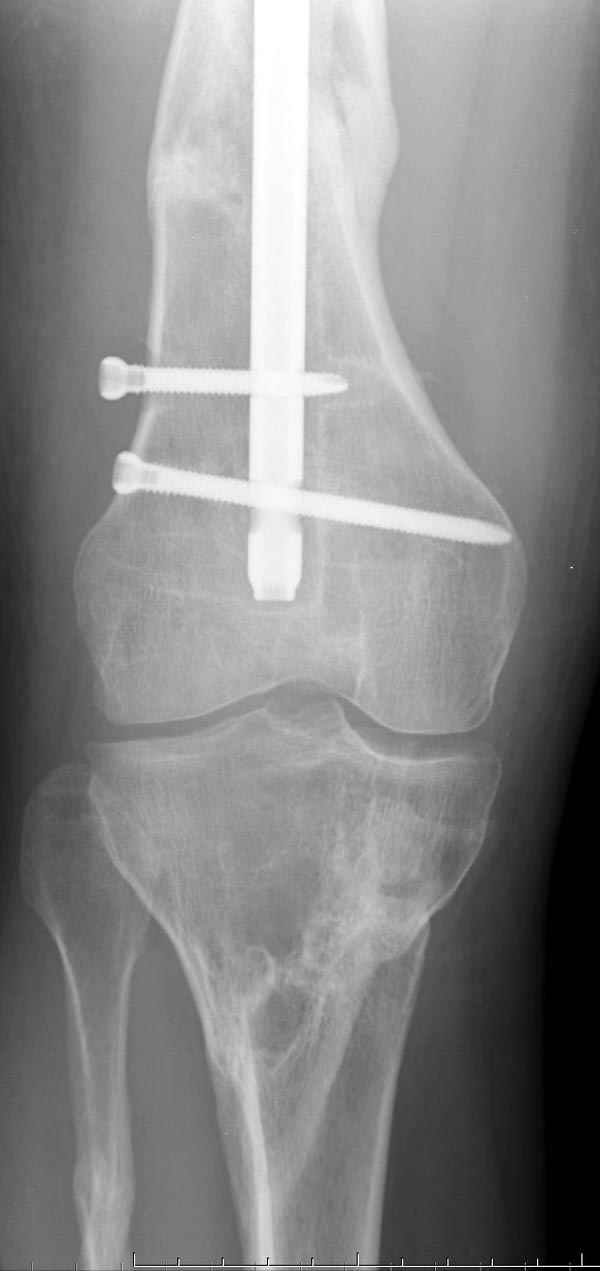

Замена реконструктивного штифта “Custom made Nail” с антибиотиком (рис №5, №6),

после промывки канала с рассверливанием внутреннего кортекса, через 4 недели антибиотический штифт удалили, оспалителный процесс остановлен и бедро сросся.

DK> При обзоре причин перелома, на снимке №2 обнаружили, что один из

DK> стержней аппарата наружной фиксации проходил только через передний

На представленных R-граммах нет снимков с АВФ. На снимке №4 дистальный статический винт не доходит до второго кортикала. Если это имелось ввиду, то хотелось бы уточнить, могло ли это привести к повторному перелому бедра, в котором интрамедуллярный штифт отсутствовал.

На снимке N2 виден канал от стержня во фронтальной плоскости, на уровне которого на снимке N7 уже перелом.